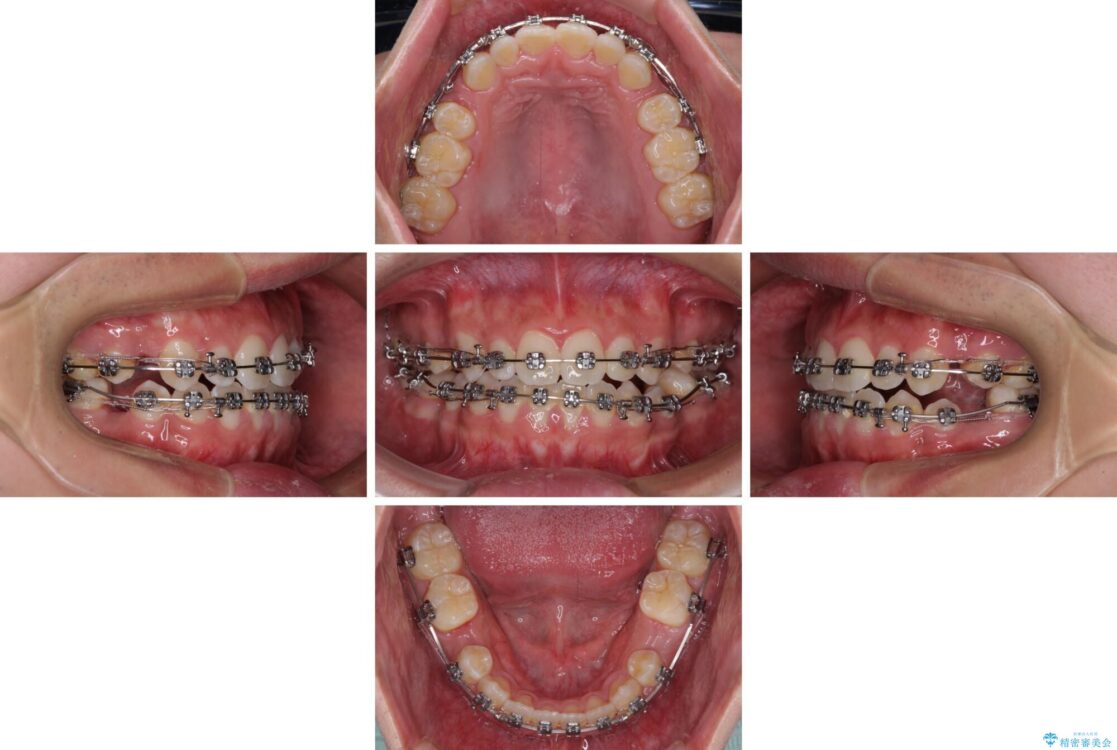

治療途中

• 口元の突出感を改善 受け口傾向の咬み合わせの抜歯矯正 治療途中画像